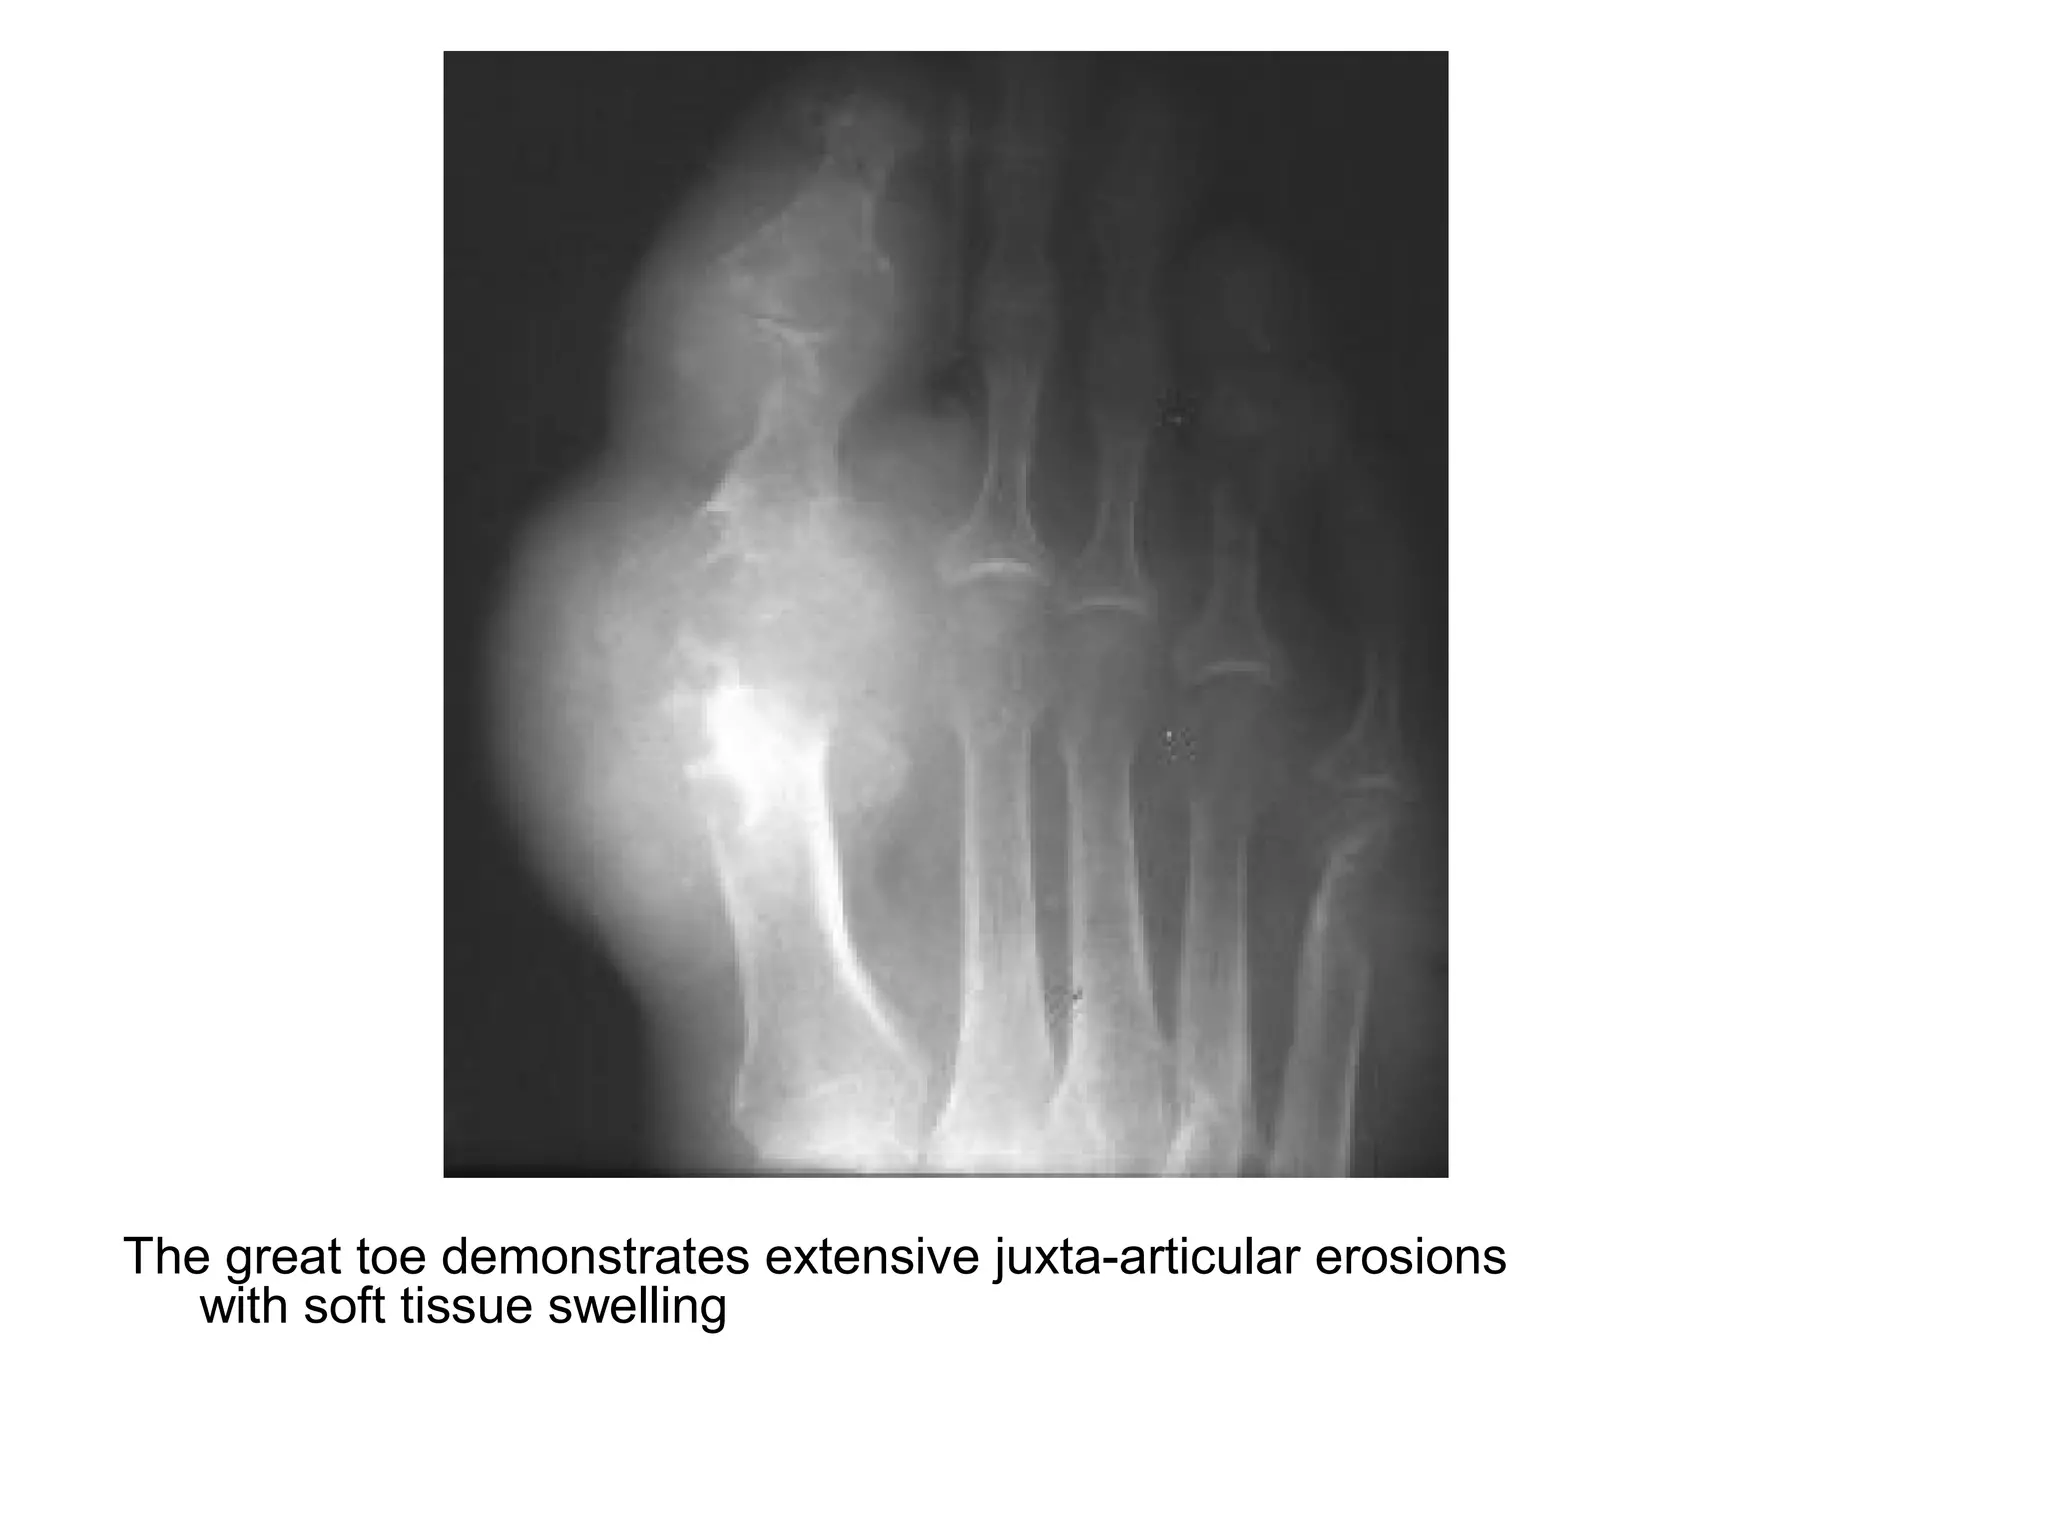

The great toe demonstrates extensive juxta-articular erosions

with soft tissue swelling